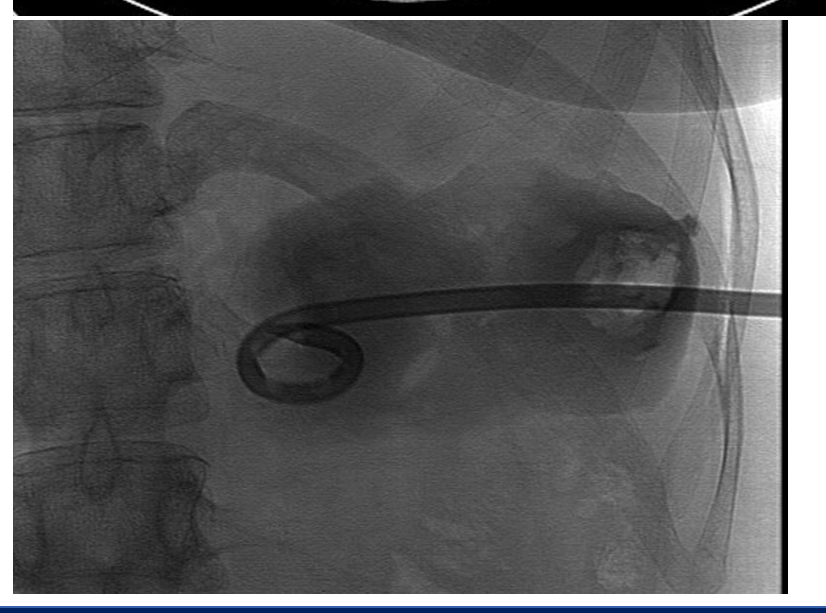

drainage could entail

*diagram shows percutanoues CT drainage*